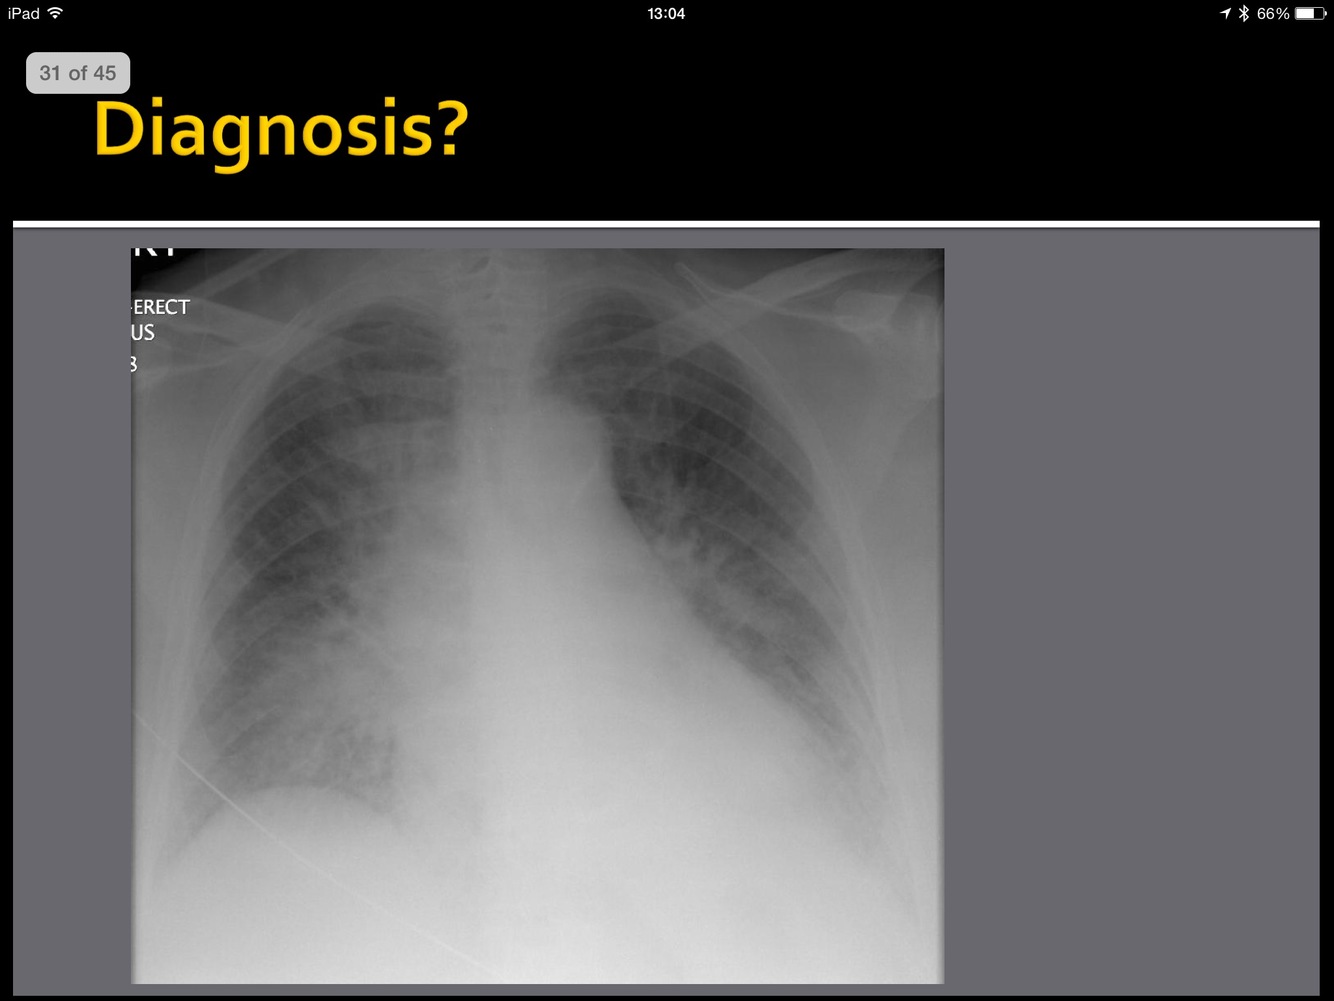

whatis the abnormality?